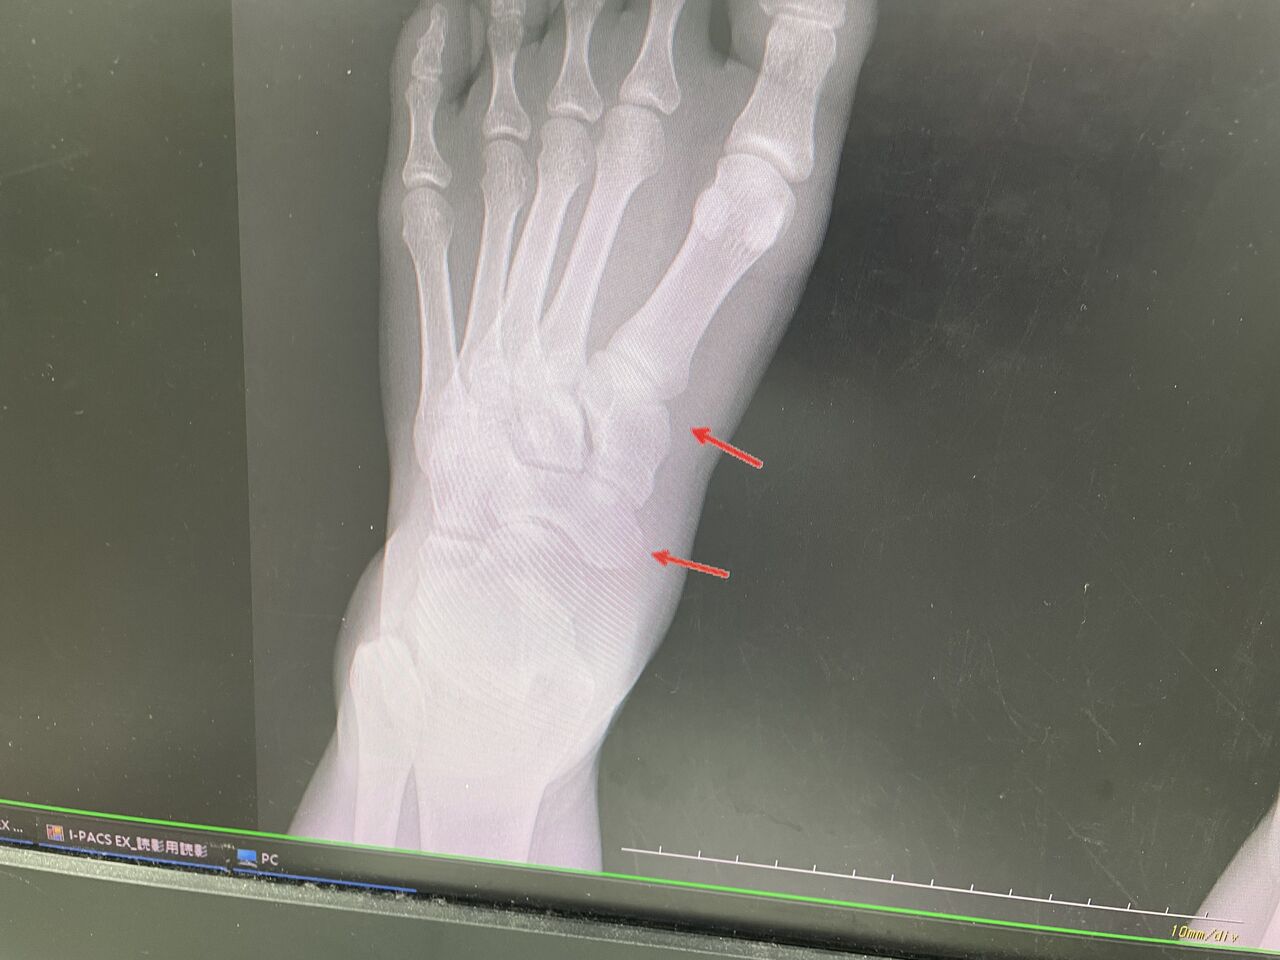

2025年03月10日 女子レスリング、アジア大会3位 某大学 女子レスリング、アジア大会3位選手 アスリートの患者さんです コリジョンスポーツなので、相手とのコンタクトが激し いですね この前、肘の靭帯を伸ばし、 治ったばかりなのに、足の怪我をしてしまいました 腫れは強く、はい強い骨折があると思いましたが、 骨挫傷と靭帯損傷で何とかなりそうです オリンピックに向けて、応援したいと思います! . カテゴリなしの他の記事 < 前の記事次の記事 >